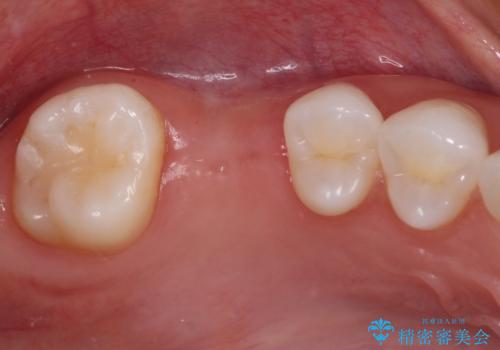

抜歯前のCTにより、インプラントを埋入するために必要な歯槽骨量が不足することが予想されたため、サイナスソケットリフトにより上顎洞内の粘膜を挙上して、インプラントを埋入することとしました。

虫歯を放置した期間が長かったため、対合の下顎大臼歯が上顎に迫ってきており、咬み合わせは非常にシビアでした。